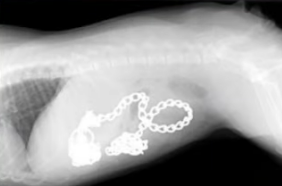

2. 이물섭취, 장중첩

두 번째는 이 물을 섭취하거나 장중첩과 같이 위나 장이 막히는 질환이 발생했을 때도 음식물이 내려가지 못하고 구토할 수 있어요